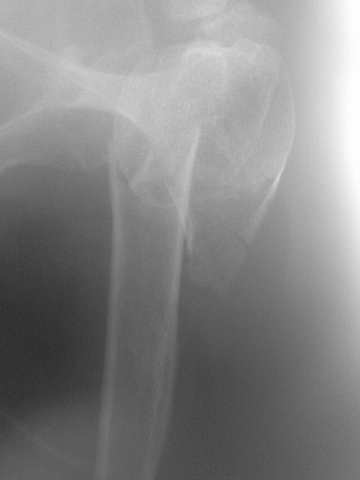

Comminuted fracture proximal humerus

Hello, I am presenting a case of 80 year old male patient right handed known case of hypertension, diabetes and history of CVA 2 years back had a fall in the hosue 10 days back and came to me for pain and ecchymosis around the right shoulder.

Xray shows evidence of comminuted fracture proximal humerus extraarticular. He is a doctors father and the doctor wants to know is there any minimally invasive procedure we can do ...

I have advised him to go for complete surgery in the form of the AO locking plate under general anesthesia.

He is a little reluctant for complete general anaesthesia.

My questions to the house is ... 1. Is there any other option besides the locking plate ?? (Less invasive)

2. If he is not medically fit for surgery, then can we leave him alone if yes what are the chances of going it into non union?